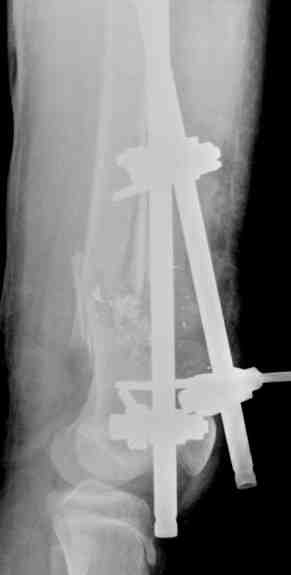

Выше приведены рентгенограммы 13-летнего подростка, страдающего от огнестрельного многооскольчатого перелома дистальной трети бедра. AO наружный фиксатор наложенный в день травмы не дал приемлемой редукции. Через три недели после перелома аппарат Илизарова был наложен без попытки одномоментной репозиции на операционном столе. There are X-Rays of a thirteen year old boy with a comminuted distal femur fracture secondary to a gunshot wound, initially treated with an AO external fixator. The alignment was unacceptable and an Ilizarov external fixator was applied three weeks after the injury. No attempt of definitive reduction was made during the surgery.

Гексаподная приставки наложена на 10 дней и приемлемая редукция была получена. The Hexapod set was applied for ten days and acceptable reduction was received.

По окончанию редукции Гексаподный сет был снят и дальнейшее ведение больного проходило в стандартном режиме аппарата Илизарова. Хороший анатомо-функциональный результат был получен. When reduction was finished, the Hexapod set was removed and further management has been continued by standard Ilizarov regime. Good anatomic and functional results were achieved.